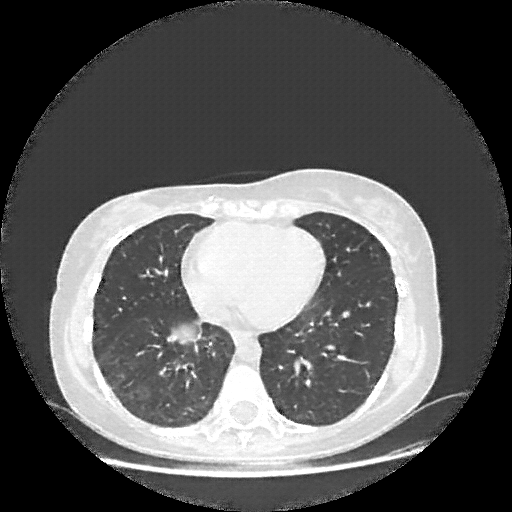

Targeted Slice 70 - Lung Window Analysis (Generated vs Real Venous)

0.720

Lung SSIM

114.8

Lung RMSE

45.1

Lung MAE

Average Lung Window Metrics Across All Slices (103 slices) - Generated vs Real Venous

0.735

Lung SSIM (Avg)

109.1

Lung RMSE (Avg)

41.9

Lung MAE (Avg)

Lung window (WL -600, WW 1500 β†’ Low βˆ’1350, High +150)